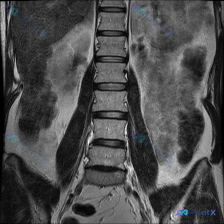

整理到一份腰椎MRI T2冠状位的影像分析,提问直接聚焦「脊柱侧弯」,但影像本身的描述有点“矛盾感”—— 客观看到的: - 椎体序列大致对齐,未见明显滑脱或侧弯畸形 - 各椎间盘T2信号弥漫性减低(脱水退变) - 椎体边缘轻度骨质增生 - 神经根、硬膜囊、骨髓信号目前看没明显急性问题 但影像总结里特...

整理到一份有意思的影像读片资料: 本来是做腰椎及肾脏的MRI-T2冠状位,主要想看肾脏情况——结果肾脏看起来倒没明显占位、积水或结石,皮髓质分界也清;但腰椎这边,第一眼扫过去椎体排列好像有点不对劲? 原报告提了椎间盘信号略减低(考虑退变),但说“整体对称性良好”;后来重新看,有人明确指出冠状位上腰椎...